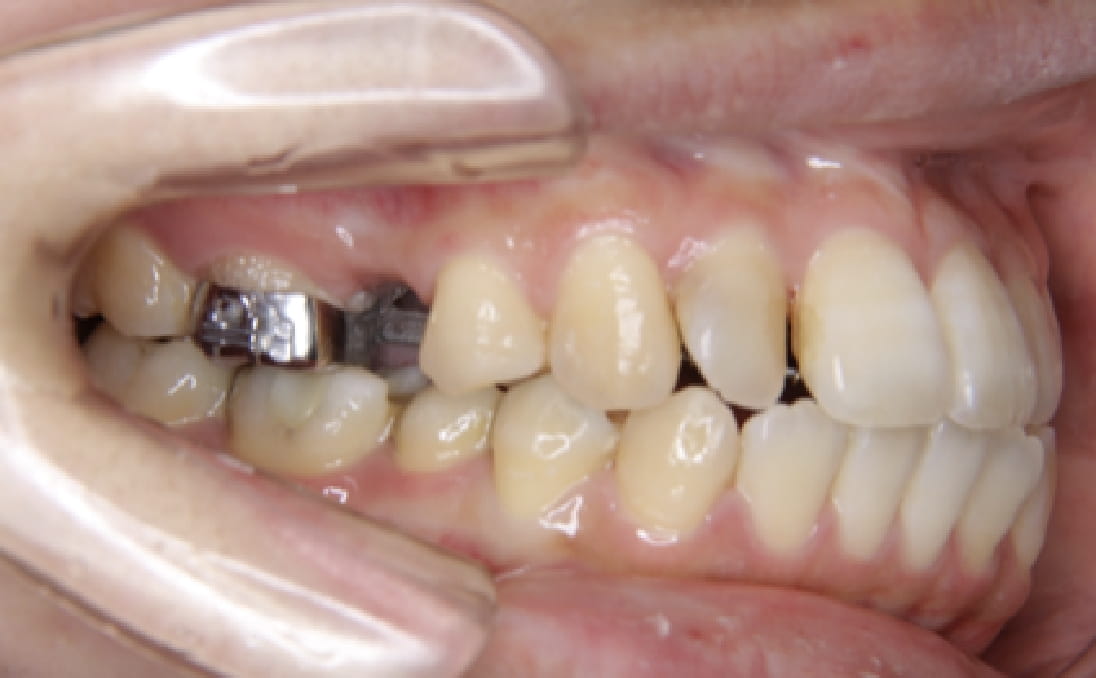

《歯槽性上下顎前突を伴う叢生》

症例42

性別:女性 年齢:13歳 お住まいの地域:奈良市

主訴 上の2本が出てるのが気になる

治療装置 上裏側、下表側からのハーフリンガル矯正装置

抜歯 上下4本

治療期間 2年8ヶ月

診断名 歯槽性上下顎前突を伴う叢生

副作用 歯肉退縮・歯根吸収・歯髄壊死・癒着による予期せぬ歯の動き

より綺麗にする希望を達成するために上下4本を抜歯。前歯のリトラクション(後方移動)を行うためにインプラントを使用。若年層ではあるが、インプラントの安定がよく、ヘッドギアに切り替えることなく、順調に進められた。

治療前

治療中(19ヶ月後)

治療中(23ヶ月後)